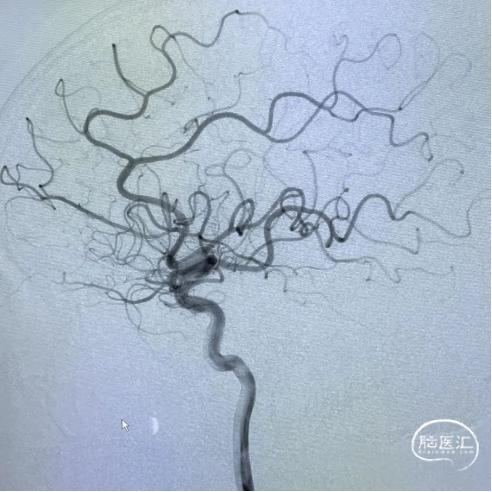

使用压力泵充盈Fastunnel®输送型球囊扩张导管扩张病变血管两次。造影见左侧大脑中动脉狭窄基本扩开。

患者血管弹性差,拟支架置入术,撤出微导丝,通过21系列 Fastunnel®输送型球囊扩张导管释放自膨式闭环支架完全覆盖狭窄血管,退出Fastunnel®,再次造影见颅内血流较术前有所改善,脑循环时间好转。遂结束手术,拔出动脉鞘压迫15分钟后加压包扎。

术后影像

术后复查头肺部CT,控制性降压,抗血小板、神经营养,对症支持治疗,继续观察。